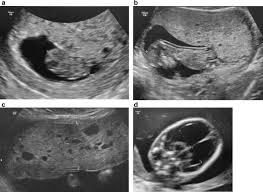

Ultrasound remains the radiological investigation of choice for initial.

The latter four entities are referred to as gestational trophoblastic neoplasia GTN. A common characteristic of all gestational trophoblastic disease is an abnormal proliferation of trophoblast but different components predominate in different tumors. Ultrasound remains the radiological investigation of choice for initial. Gestational trophoblastic neoplasia GTN encompasses a broad spectrum of placental lesions from the pre-malignant hydatidiform mole complete and partial through to the malignant invasive mole choriocarcinoma and rare placental site trophoblastic tumour PSTT. The latter four entities are referred to as gestational trophoblastic neoplasia GTN. There are several histologically distinct types of GTD that range from premalignant complete and partial hydatidiform moles HMs to malignant diseases also known as gestational trophoblastic. Ultrasound in the Diagnosis and Management of GTN Gestational trophoblastic neoplasia GTN includes invasive mole choriocarcinoma PSTT and ETT. Because it is an unusual and serious disease that affects women of reproductive age as well as because its appropriate treatment results in high cure rates it is crucial that radiologists be familiar with gestational trophoblastic disease in order to facilitate its early diagnosis and to ensure appropriate follow-up imaging. Gestational trophoblastic disease GTD is a spectrum of both benign and malignant gestational tumors including hydatidiform mole complete and partial invasive mole Choriocarcinoma placental site trophoblastic tumor and epithelioid trophoblastic tumor.

Gestational trophoblastic disease GTD encompasses a heterogeneous group of lesions including hydatidiform mole invasive mole choriocarcinoma and placental site trophoblastic tumor Mazur and Kurman 1994. The term gestational trophoblastic disease GTD encompasses a spectrum of tumors with a wide range of biologic behavior and potential for distant metastases. Gestational trophoblastic disease GTD is a term used for a group of pregnancy-related tumours. GTD refers to both the benign and malignant entities in the spectrum and includes hydatidiform mole complete and partial invasive mole choriocarcinoma placental site trophoblastic tumor PSTT and epithelioid trophoblastic tumor ETT. There are several histologically distinct types of GTD that range from premalignant complete and partial hydatidiform moles HMs to malignant diseases also known as gestational trophoblastic. Ultrasound in the Diagnosis and Management of GTN Gestational trophoblastic neoplasia GTN includes invasive mole choriocarcinoma PSTT and ETT. GTD refers to both the benign and malignant entities in the spectrum and includes hydatidiform mole complete and partial invasive mole choriocarcinoma placental.